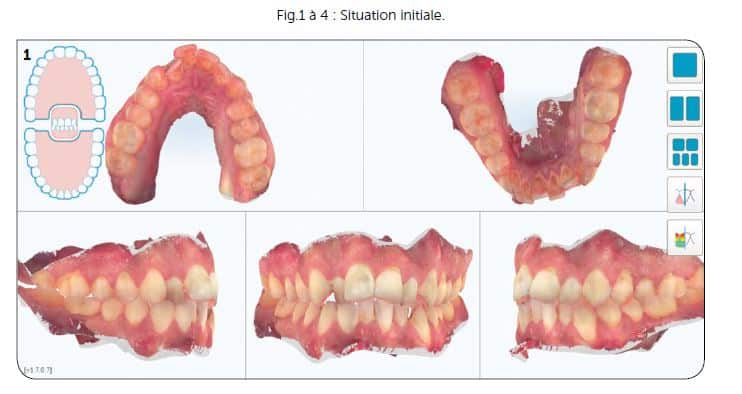

Un patient de 30 ans vient au cabinet pour un encombrement de sa zone antérieure tant maxillaire que mandibulaire. À l’examen clinique, hormis sa DDM, il était en classe 1 molaire des deux côtés, facilitant la prise de décision dans son plan de traitement (Fig.1 à 4).

Suites aux examens, nous avons réalisé un premier ClinCheck permettant d’avoir un premier repositionnement (Fig.5). On peut ici constater :

– une série de 17 aligneurs,

– une série de réductions inter-proximales maxillaires (RIP) pour un total de 1,0 mm réparties entre les 15 et 25,

– une série de réductions inter-proximales mandibulaires (RIP) pour un total de 0,8 mm réparties entre les 15 et 25,

–des taquets répartis sur toutes les dents maxillaires pour optimiser les mouvements voulus,

– des taquets sur quelques dents maxillaires.

La durée du traitement est de 34 semaines avec un changement des aligneurs toutes les 2 semaines (Fig.5 à 7).